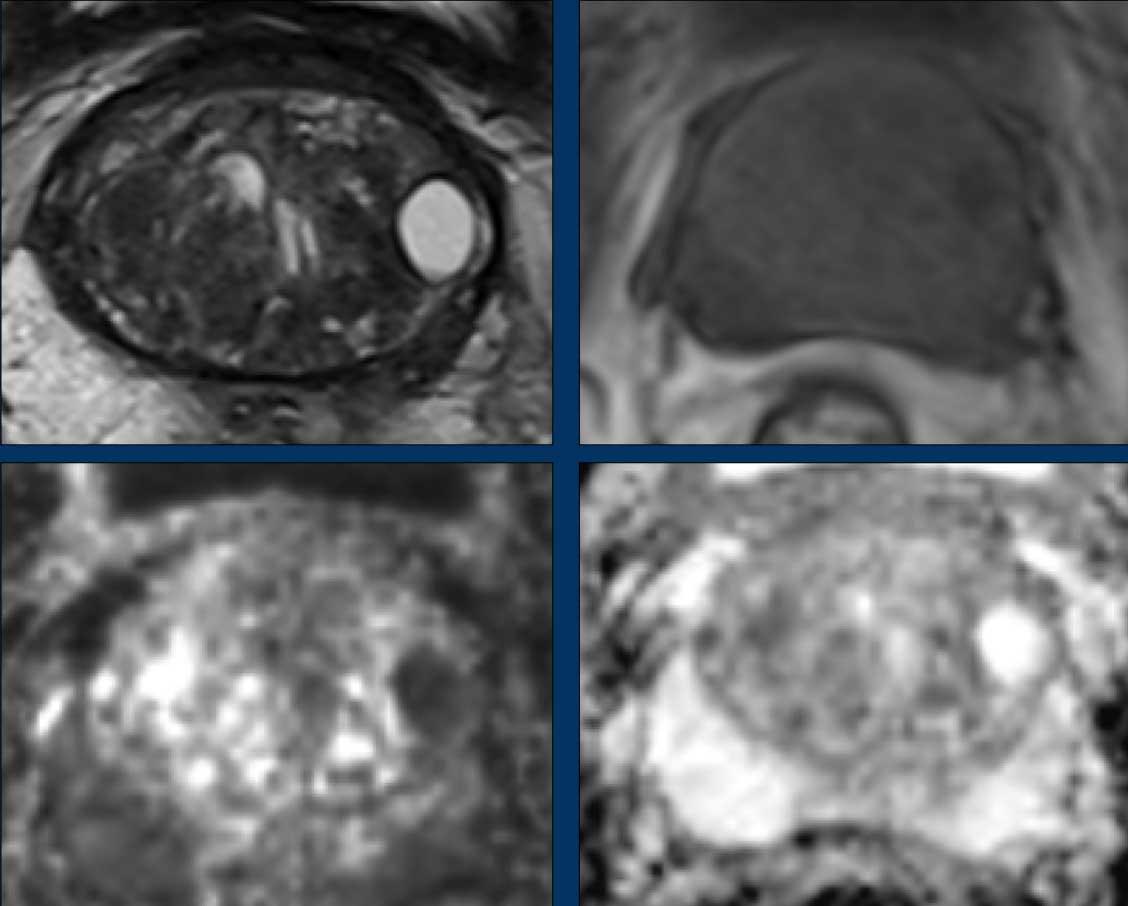

Ung thư tuyến tiền liệt tại vùng ngoại vi (PZ)

Đối với vùng ngoại vi, chuỗi xung DWI/ADC là chuỗi xung chính để xác định phân loại đánh giá PI-RADS.

Hãy quan sát hình ảnh trước và mô tả những gì bạn thấy.

Một tổn thương kích thước 16 mm (không hiển thị phép đo) được phát hiện, nằm ở phía sau vùng ngoại vi của phần giữa tuyến tiền liệt bên phải.

Tổn thương này được xếp vào phân loại PI-RADS 5, dựa trên giảm tín hiệu rõ rệt trên ADC và tăng tín hiệu rõ rệt trên DWI (điểm 5 – chuỗi xung chính), đối chiếu với giảm tín hiệu rõ rệt trên chuỗi xung T2W (điểm 5).

Điểm Gleason là 3+4, cho thấy nguy cơ trung bình của một ung thư có tính xâm lấn cao.

Tổn thương không tiếp xúc với vỏ bao giả và không có dấu hiệu xâm lấn ra ngoài tuyến tiền liệt.

Hãy quan sát hình ảnh trước rồi tiếp tục đọc.

Các phát hiện bao gồm:

- Một tổn thương kích thước 17 mm (không hiển thị phép đo) nằm ở vùng ngoại vi, phía sau bên trái của phần giữa tuyến tiền liệt.

- Giảm tín hiệu rõ rệt trên ADC và tăng tín hiệu rõ rệt trên DWI.

- Tương ứng với vùng giảm tín hiệu trên chuỗi xung T2W.

- Trên chuỗi xung T2W, tổn thương tiếp xúc diện rộng với vỏ bao tuyến tiền liệt.

Tổn thương này được xếp vào phân loại PI-RADS 5 với nghi ngờ xâm lấn ra ngoài tuyến tiền liệt.

Điểm Gleason là 4+3.

Tổn thương nghi ngờ này có hạn chế khuếch tán đáng kể.

Giá trị ADC đo được là 440 mm²/s.

Giá trị ADC thấp cho thấy nguy cơ ác tính cao hơn.

Giá trị ADC thực tế có tương quan nghịch với khả năng ác tính có ý nghĩa lâm sàng.

Các giá trị trên 900 mm²/s được coi là có khả năng lành tính và dưới 750 mm²/s có khả năng ác tính.

Tuy nhiên, kết quả định lượng có thể khác nhau đáng kể giữa các máy chụp và các giao thức chụp.